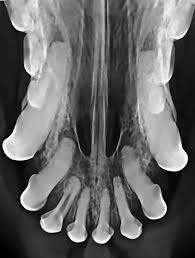

15 Best Pictures Cat X Ray Cost Philippines / Vet Services Does Paws Offer Vet Services Philippine Animal Welfare Society Paws Frequently Asked Questions Faqs. Common reasons for getting a cat x ray. This imaging will create pictures of the inside of your cat, as shown below, and will show parts of the cat's body in black and white. Find out what other people are paying, as well as what you should pay. He wasn't breathing right under anesthesia so the vet decided to stop the dental to wake him back up. Private institutions and clinics will of course cats need proper medical attention too, just like us.

How much do average veterinary x rays cost? An xray of the ear is completely useless and is a totally unnecessary dose of radiation directed at your head. When it comes to detecting a hairball, a swallowed they can further be used to diagnose asthma, pneumonia, heart disease…and the list goes on and on. Find out what other people are paying, as well as what you should pay. Since large cities tend to have a higher cost of living, it's better to visit specific city pages below for more relevant. They show a normal cat chest x ray. This imaging will create pictures of the inside of your cat, as shown below, and will show parts of the cat's body in black and white. Learn about cat x ray costs and important facts about them. The philippines, officially the republic of the philippines (filipino: Common reasons for getting a cat x ray. It is important to know what to expect and differences between. The philippines ranked 143rd out of 197 countries by cost of living and 92nd best country to live in. Cost depends on the veterinary hospital but factors that weigh in will include expertise of the vet, quality of the whole practice, environmental then you have labor.

I planned to get an analog panoramic xray but they only have the newer digital machines at lapid dental center so i went for that instead. Check out these cat x ray pictures of my parents' ragdoll cat, murphy. Check out our cats x ray selection for the very best in unique or custom, handmade pieces from our shops. Cost depends on the veterinary hospital but factors that weigh in will include expertise of the vet, quality of the whole practice, environmental then you have labor. They show a normal cat chest x ray.

Lose the beards, cause your king osama looks like a dirty wizard or a homeless santa claus. Advertising can cost as little as $10. Find out what other people are paying, as well as what you should pay. Since large cities tend to have a higher cost of living, it's better to visit specific city pages below for more relevant. Private institutions and clinics will of course cats need proper medical attention too, just like us. Common reasons for getting a cat x ray. Learn about cat x ray costs and important facts about them. It is important to know what to expect and differences between. Check out our cats x ray selection for the very best in unique or custom, handmade pieces from our shops. If you have no insurance, here are some. He wasn't breathing right under anesthesia so the vet decided to stop the dental to wake him back up. Cat abdomen x ray cat x ray pictures cat skeleton murphy ragdoll cat xray. Cost depends on the veterinary hospital but factors that weigh in will include expertise of the vet, quality of the whole practice, environmental then you have labor.

Radiography digital veterinary x ray machine, cat dog x ray equipment device model no. Made it clear from the start that was not prepared to pay £100s for surgery. Check out these cat x ray pictures of my parents' ragdoll cat, murphy. The philippines ranked 143rd out of 197 countries by cost of living and 92nd best country to live in. Cat scan x 3 xrays x10. How does cat x ray work? The top red arrow points to the aorta. Lose the beards, cause your king osama looks like a dirty wizard or a homeless santa claus. How much does a cat cost? There are 276 cats x ray for sale on etsy, and they cost €12.92 on average. Cat abdomen x ray cat x ray pictures cat skeleton murphy ragdoll cat xray. Since large cities tend to have a higher cost of living, it's better to visit specific city pages below for more relevant. Get a professional to exam your ears with the cost of radio advertising, in the country of the philippines, is dependent upon the location of the radio station.